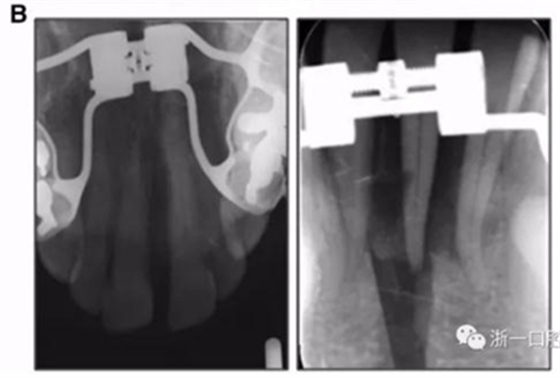

全麻下進(jìn)行上頜骨腭中縫骨皮質(zhì)劈開(kāi)及下頜正中劈開(kāi)術(shù)。手術(shù)后,用X光片檢查上頜骨和下頜骨中線(xiàn)切口的位置和方向。

術(shù)后第9天開(kāi)始旋轉(zhuǎn)擴(kuò)弓器,每天轉(zhuǎn)2次,每次轉(zhuǎn)90度,即擴(kuò)開(kāi)0.5mm。每隔1周進(jìn)行檢查,目標(biāo)上頜擴(kuò)開(kāi)9mm,下頜擴(kuò)開(kāi)6mm。18天后,上頜中切牙間出現(xiàn)8mm間隙。下頜出現(xiàn)6mm間隙,(于13天出現(xiàn)后,停止旋轉(zhuǎn)擴(kuò)弓器)。在擴(kuò)弓器旋轉(zhuǎn)3天后,拍片發(fā)現(xiàn)左下頜中切牙遠(yuǎn)中牙根中段有一條低密度陰影,臨床冷熱診反應(yīng)遲鈍,可能為術(shù)中損傷所致。牙體牙髓科會(huì)診,建議行根管治療,故行根管治療。